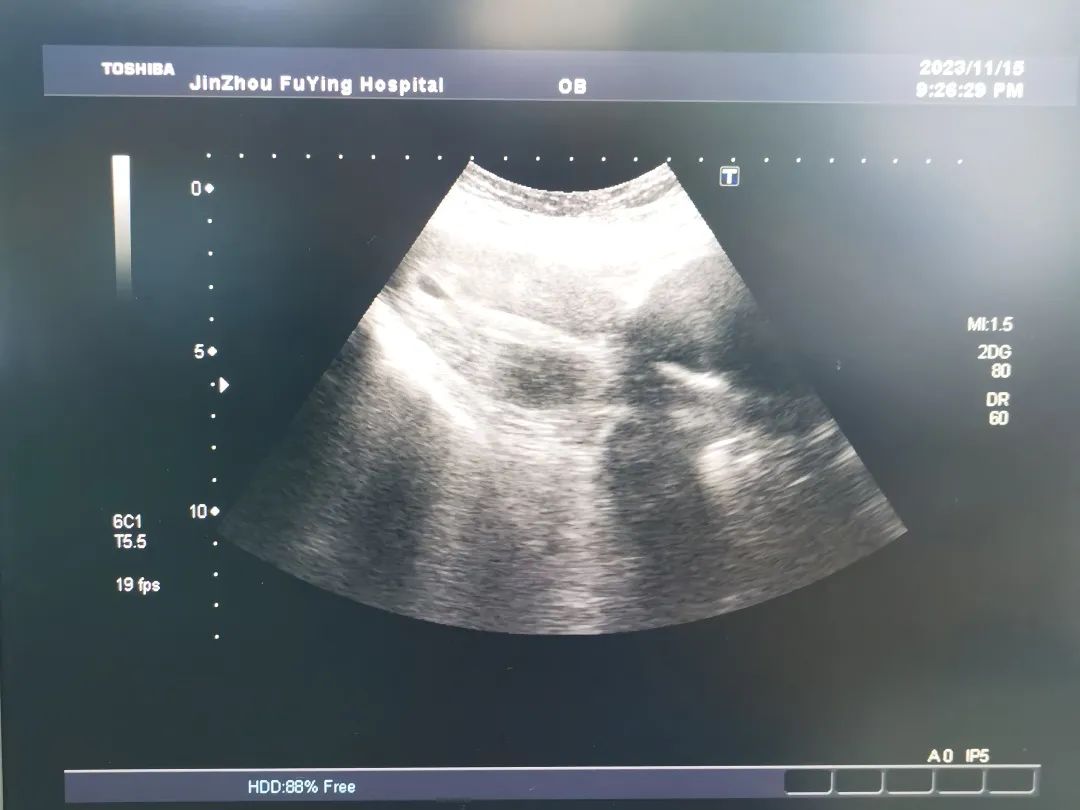

11月16日,计划生育科来了一位特殊的手术患者。该患者3天前在当地医院就诊要求行人工流产手术,因术前超声检查提示“巨大子宫颈肌瘤“,当地医院考虑手术困难,被拒绝手术,遂来我科诊治。

门诊医生详细询问患者病史,“患者妊娠8周”,内诊宫颈前壁可触及约7.0×5.0cm肿物,宫颈被压迫变形,评估手术难度大,引起我科高度重视;人流手术室金医生在看到病志后,再次对患者病情进行评估,巨大子宫颈肌瘤压迫宫颈导致宫颈管变形、狭窄可能带来的一系列风险,如进入宫腔困难等,在术前请超声科会诊并对术中可能发生的情况进行讨论后,向患者及家属详细交代病情、讲解手术的难度及风险。经过医生与患者及家属的反复交代沟通后,在患者及家属的信任与期待中,手术平稳有序的开始了……